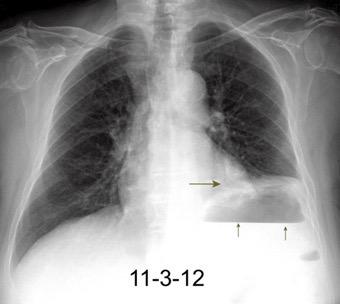

Accidente de tráfico

Rx: Niveles hidroaéreos en hemitórax izquierdo Desviación mediastínica Ausencia de intestino en abdomen. Configuración en reloj de arena del intestino herniado “Tubo nasogástrico”

Furak J et al. Diaphragm and transdiaphragmatic injuries. J Thorac Dis 2019

Diafragma “colgante” (“dangling sign”)

(“Dangling sign”)

TC. Mejor con multicorte. (reconstrucciones).

Asociación: Aire en pared.

Fracturas costal .Rotura esplénica. Neumoperitoneo.

Diafragma discontinúo Herniación de la grasa omental

Desser TS et al.The dangling diaphragm sign: sensitivity and comparison with existing CT signs of blunt traumatic diaphragmatic rupture. Emerg Radiol 2010